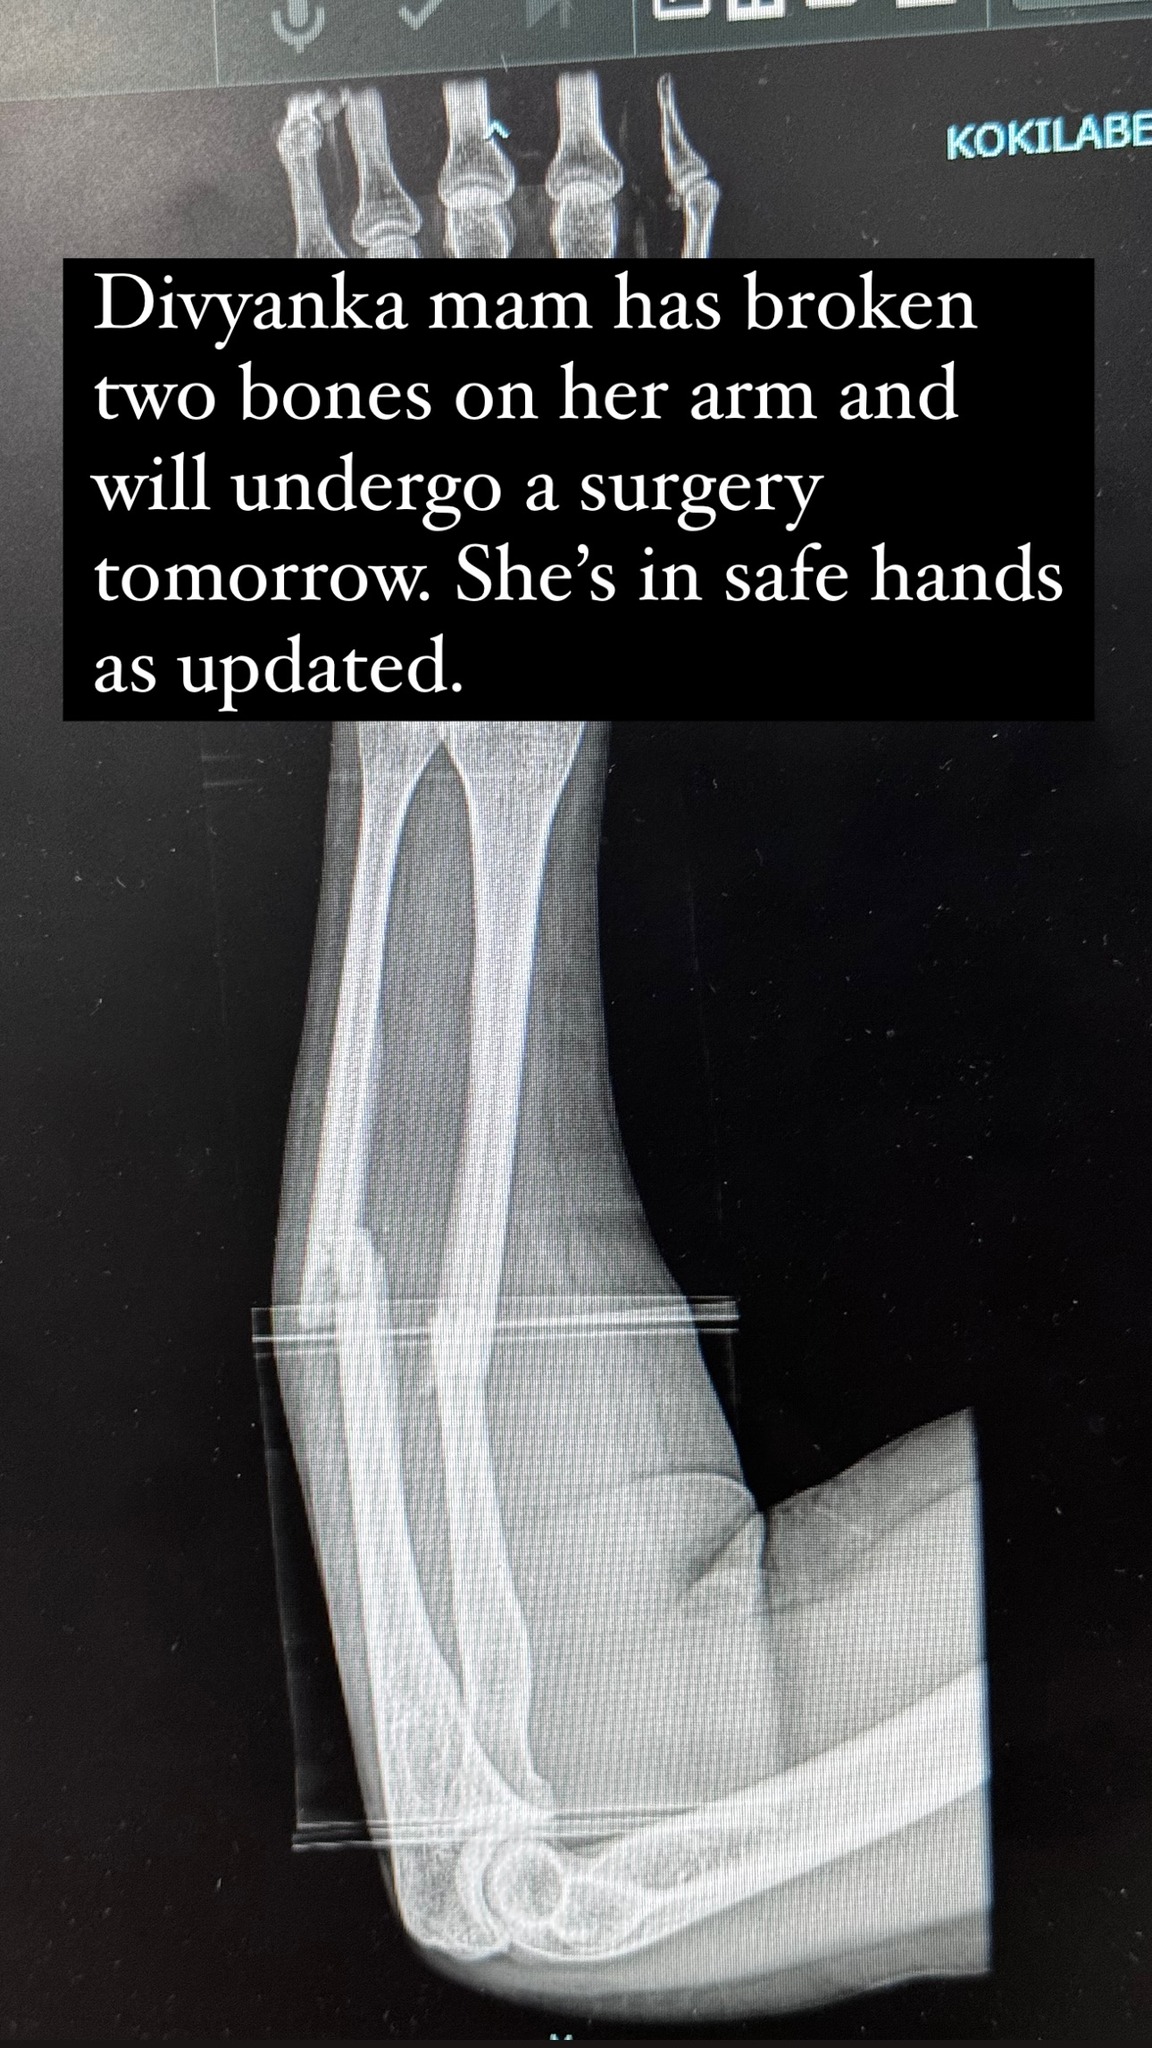

On April 18, Vivek shared an Instagram story, which read, “Divyanka mam has broken two bones on her arm and will undergo surgery tomorrow. She’s in safe hands as updated (sic).”

Television actress Divyanka Tripathi was rushed to a hospital after she met with an accident. The news has been informed by the actress’ PR team and husband Vivek Dahiya. He had shared an image of an X-ray informing Divyanka had broken two bones in her arm and would undergo surgery today.

A while ago, Vivek Dahiya took to his Instagram stories and shared an update about Divyanka’s health. He wrote, “Divyanka is on her road to recovery. A Mishap occurred last evening where she fell from a height due to which she broke both her forearm bones and was advised immediate surgery.” He continued, “We appreciate all the love and prayers being bestowed upon us it means a lot. To all our fans and media friends thank you for the immense love and concern. While Divyanka is in pain but only to recover from it hereon we would love for her to do so in the privacy of her home and family.“